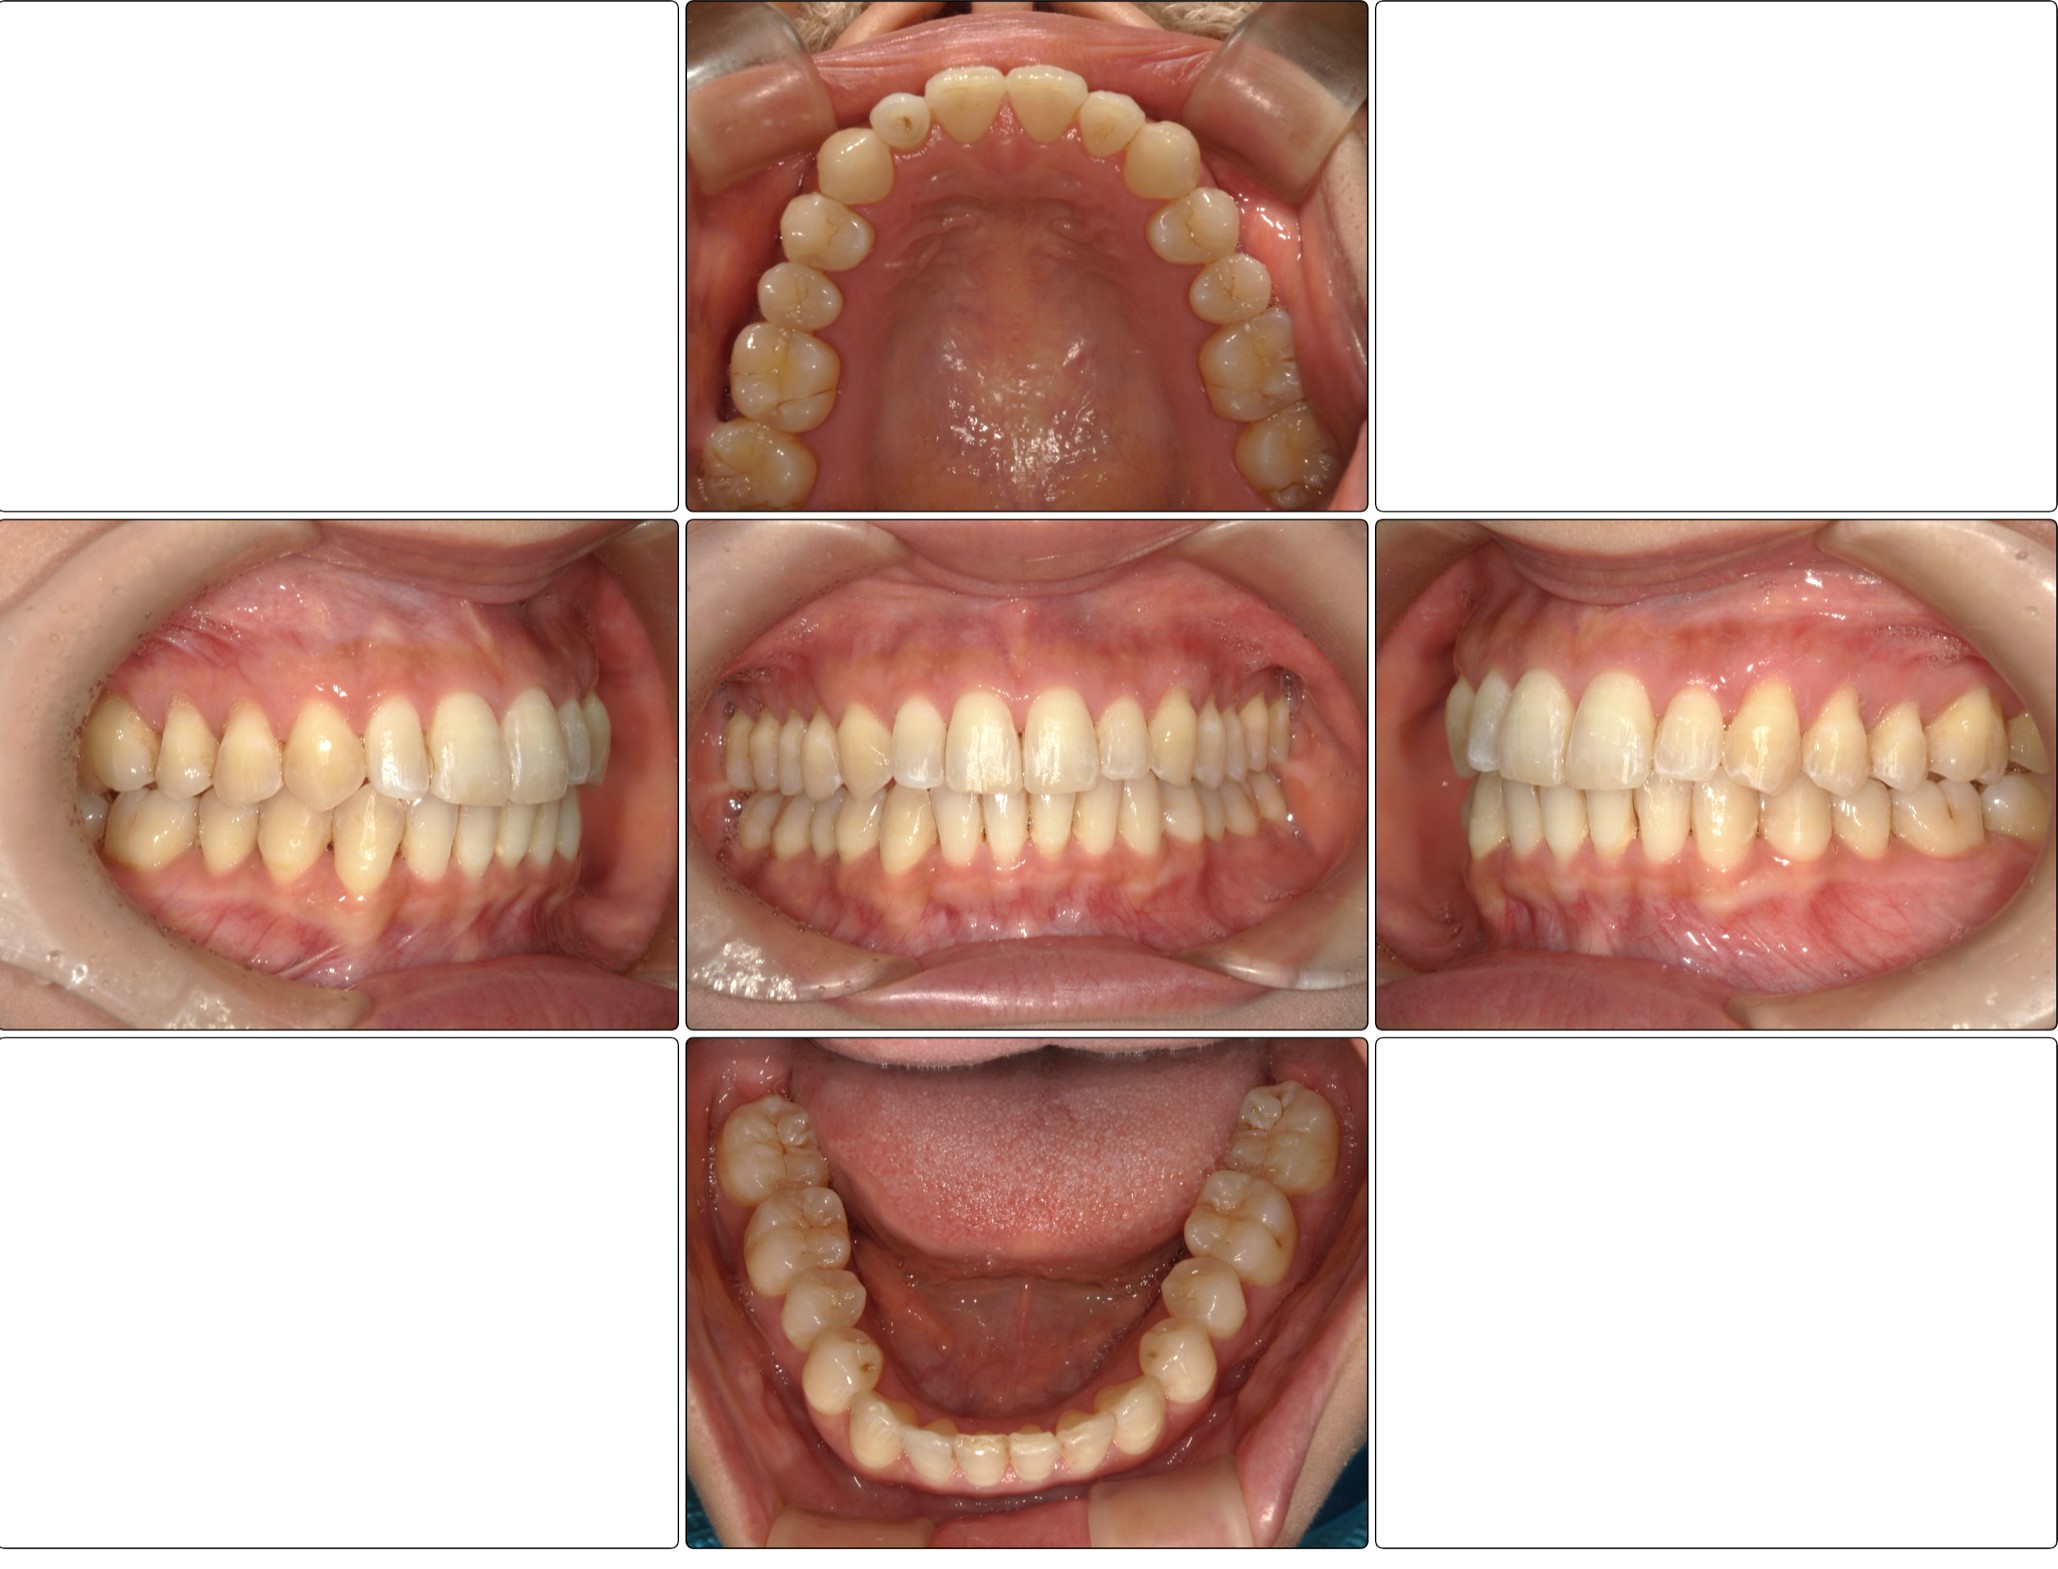

お口の中全体の写真

After

| 治療に関する情報 | 下の前歯のガタツキ並びに全体の歯並びをインビザラインで矯正したケースです。 |

| 治療結果 | 下の歯列のガタツキは改善され、大きかった歯間の隙間も閉じました。 |